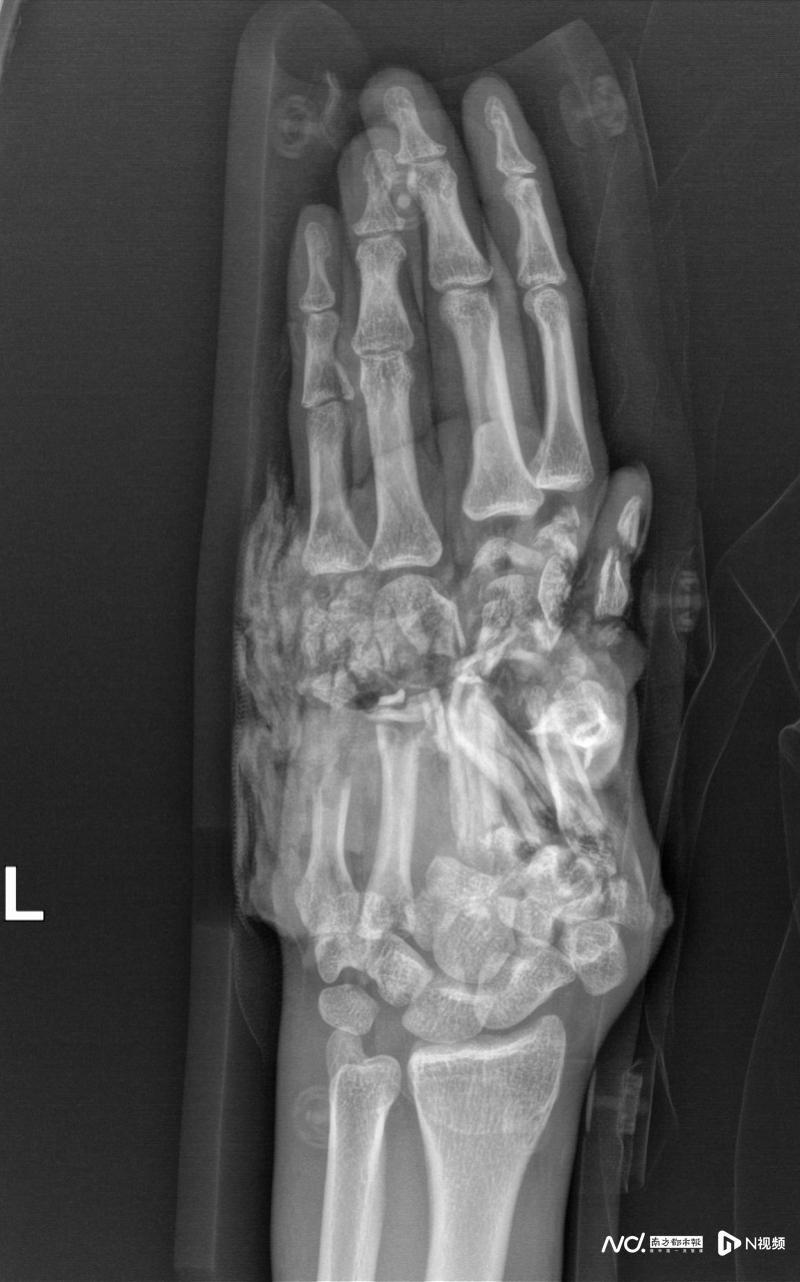

影像檢查提示,傷者的左手掌已經(jīng)被巨大的力量毀損得支離破碎。

當(dāng)?shù)蒯t(yī)院緊急包扎后,醫(yī)生坦言傷勢過重?zé)o法處理。王先生當(dāng)即決定轉(zhuǎn)院,于當(dāng)天上午11點多抵達廣州和平骨科醫(yī)院。創(chuàng)傷顯微外一科主任王小立團隊接診時發(fā)現(xiàn),患者左手1-5掌骨粉碎性骨折,手背及腕部皮膚大面積撕脫,血管、神經(jīng)、肌腱多處斷裂,創(chuàng)面污染嚴重。“左手已因失血和創(chuàng)傷瀕臨壞死,保肢難度極大。”參與救治的何天頌醫(yī)生回憶,但患者保肢意愿極其強烈:“無論如何,請你們試一試!”